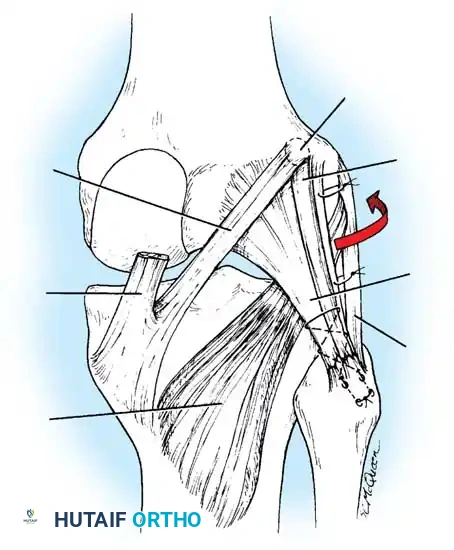

Lateral Collateral and Posterolateral Corner (PLC) Repair

Lateral-sided injuries are notoriously unforgiving and rarely heal with conservative management due to the inherent varus alignment of the lower extremity during the normal gait cycle.

A curvilinear incision is made over the lateral aspect of the knee, incorporating the iliotibial band and the biceps femoris. The common peroneal nerve must be identified, neurolysed, and protected with a vessel loop throughout the procedure.

Image

The LCL, popliteus tendon, and popliteofibular ligament are systematically evaluated. Avulsions from the fibular head are common.

Deep capsular tears are repaired with interrupted sutures. If the LCL or popliteus is avulsed from the lateral femoral epicondyle, anatomical footprints are identified, and the structures are repaired using suture anchors. Tensioning must be performed with the knee in 30 degrees of flexion and neutral rotation.

In cases where the native tissue is non-viable or the injury is subacute, an anatomical posterolateral corner reconstruction using an autograft or allograft (e.g., Achilles or semitendinosus) is mandated. The graft is routed to recreate the LCL and popliteofibular ligament.

Robust fixation is achieved using interference screws or screw-and-washer constructs in the fibular head and lateral femoral condyle. The biomechanical integrity of the construct is verified by taking the knee through a full range of motion, ensuring no impingement or laxity.